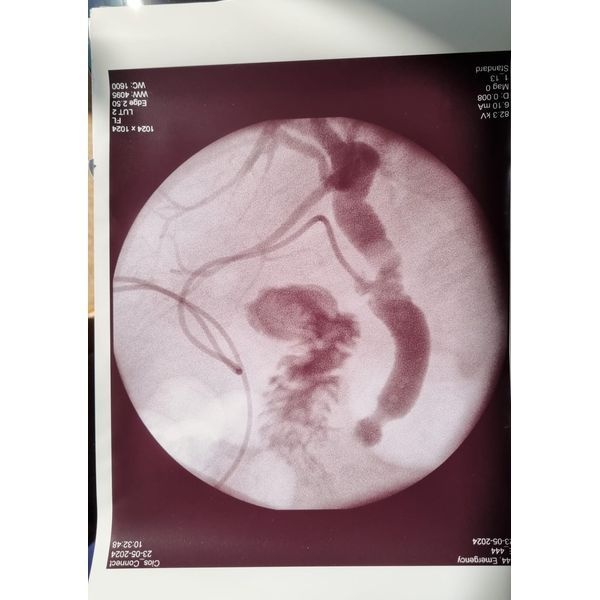

В желчном пузыре также обнаружились камни. Так как у женщины были признаки желтухи, ранее камни могли попасть в холедох — общий желчный проток. Учитывая это, ей также провели дренирование холедоха через культю пузырного протока, чтобы снизить давление желчных путей и выполнить фистулографию (рентгеноконтрастное исследование).

Фистулография подтвердила наличие камней в желчном протоке (холедохолитиаз).

На основании выявленной находки было принято решение провести ещё одну операцию на следующий день: эндоскопическую папиллосфинктеротомию и холедохолитоэкстракцию — разрез большого дуоденального сосочка и извлечение камней из протока.

Послеоперационный период протекал без осложнений. На контрольной фистулографии конкрементов в холедохе не было, дренаж перевязали.